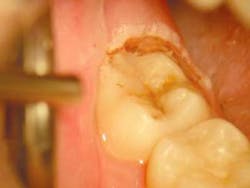

Often when a general dentist is restoring lower molars, an operculum can be found which can hinder his or her restorative endeavors (Fig. 1). The perfect tool for removing this operculum and assisting the dentist is the soft-tissue laser. The soft-tissue laser can remove the offending operculum atraumatically, often with little or no anesthesia and no postoperative discomfort or bleeding. Those who practice microdentistry with air abrasion or a hard-tissue laser can be particularly assisted by the durable hemostasis afforded by a soft-tissue laser. Those dentists who are familiar with hard-tissue lasers know that, although soft-tissue surgery is possible with the Erbium wavelengths, the hemostasis that is afforded can be negligible in all but the healthiest tissues. This is a fact that is supported by the physics of the wavelengths. The author, who is a lecturer for bioLitec is particularly excited by the excellent tissue effects, no charring and durable hemostasis, that are derived by the 980nm wavelength of the bioLitec SmilePro 980. This wavelength has the highest water absorption of all of the near-infrared wavelengths. Since tissue is comprised of nearly 60 to 80 percent water, water absorption is a valuable property in tissue-cutting lasers.

The tooth in question (#31) is to be treated by micro-air-abrasion, which is being more widely accepted due to the efforts of J. Tim Rainey, The Society for Advanced Microdentistry, and, alternatively, members of the Congress of Microdentistry, Kim Kutsch, Stewart Rosenberg, Graeme Milicich, and others. Forgive me, if I've left your name from the list or if I've placed them in an incorrect order. The work performed is facilitated by the use of a Seiler surgical operating microscope, a necessary adjunct for any dentist practicing minimally invasive dentistry or, in the author's opinion, any form of dentistry. Magnification can greatly improve any dentist's results regardless of the acuity if his or her vision and is being addressed in several of the more progressive dental schools across the country.